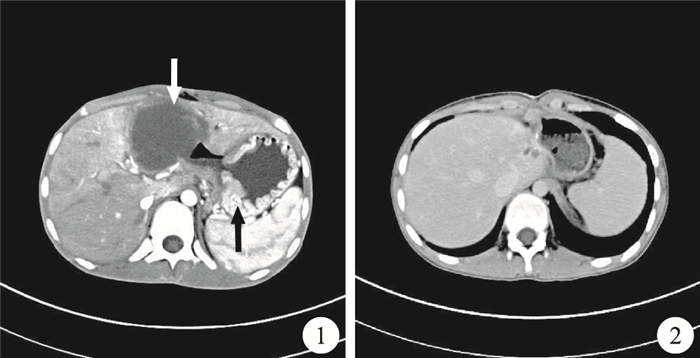

病例資料 患者,男,14歲,因“腹痛、消瘦及低熱3個月”入院。查體:生命體征正常,體溫38.0 ℃;呈重度營養不良表現,嚴重消瘦,凹型腹;上腹部劍突下見微隆起,可觸及一實質性包塊,較硬,約4.0 cm×5.0 cm大,上腹部有壓痛,無反跳痛。腹部CT檢查:肝左外葉見2個橢圓形低密度影,分別約65.5 mm×55.5 mm和85.0 mm×55.0 mm大,邊界欠清,其內均見分隔影;增強后2個病灶均呈持續性環形強化,壁較厚,其內分隔影見強化,而低密度影無強化;胃腔內胃底處胃壁明顯增厚,增厚的胃壁強化不明顯,其中心有局限性缺損并通至胃腔外,與肝左葉低密度影相連(圖 1);腹腔內多發腫大淋巴結。胃鏡檢查:環胃壁半周有一巨大潰瘍(約10.0 cm×10.0 cm大),底部可見厚白黃苔及污苔形成(直徑3.0 cm);潰瘍周圍未見縫隙與瘺管相通。取胃壁組織送病理學檢查,示胃體炎性肉芽組織及炎性壞死滲出物,局灶性異物巨細胞反應。初步診斷為:胃占位、胃穿孔、惡性腫瘤肝轉移。遂行剖腹探查術,術中見肝左葉明顯增大,內可觸及2個較大腫物,分別位于靠近膈面及第一肝門附近,分別為7.0 cm×6.0 cm×5.3 cm及9.0 cm×6.2 cm×4.5 cm大,包塊表面呈灰黃色,邊界不清楚,質硬;第一肝門處腫塊突出到肝胃韌帶內,并緊貼胃小彎;小腸系膜可觸及大量黃豆大小的腫大淋巴結。術中取胃組織送冰凍病理學檢查示淋巴瘤,遂行左半肝切除術、近端胃(包括胃小彎潰瘍及穿孔在內)切除術。術后病理學檢查示,胃小彎彌漫性大B細胞淋巴瘤、肝轉移。臨床診斷:胃惡性淋巴瘤并巨大潰瘍穿孔,肝臟多發巨大轉移瘤。患者術后應用CHOP方案化療4個療程。術后恢復良好,未出現并發癥。術后獲訪1年,行腹部CT檢查未發現腫瘤復發及轉移(圖 2)。

討論 原發性胃惡性淋巴瘤(primary gastric malignant lymphoma,PGML)少見,僅占胃惡性腫瘤的1%~4%。首先表現為胃腸道受累癥狀的淋巴瘤稱為原發性胃腸道惡性淋巴瘤,占全部淋巴瘤的5%。內鏡檢查是目前診斷胃部疾病的主要手段,內鏡下PGML具有以下特點:①病變范圍廣,累及多個部位,表現為大的潰瘍、巨大的腔內腫物、廣泛多發的結節、鵝卵石樣外觀或彌漫性分布顆粒型改變;②病變多發,表現為多發性潰瘍或多灶性損害時應考慮該病。但由于這些表現缺乏特異性,且PGML往往原發于黏膜下,胃鏡活檢的陽性率為40%~50%。本例患者術前行胃鏡檢查未發現腫瘤組織,故內鏡醫師對內鏡下有上述表現者應予以重視。有報道認為,胃惡性淋巴瘤的轉移途徑與胃癌相仿,主要為直接蔓延和經淋巴途徑,經淋巴途徑轉移的發生率為40%~50%。根據惡性淋巴瘤的生物學行為特性,其很少侵犯鄰近臟器,即使與周圍臟器有粘連也是非侵襲性的。因此,本例出現的肝臟侵襲性轉移較為少見。胃淋巴瘤應以手術治療為主,輔以化療、放療和生物治療,并應根據組織學類型和臨床病理分期擬定個性化的治療方案。